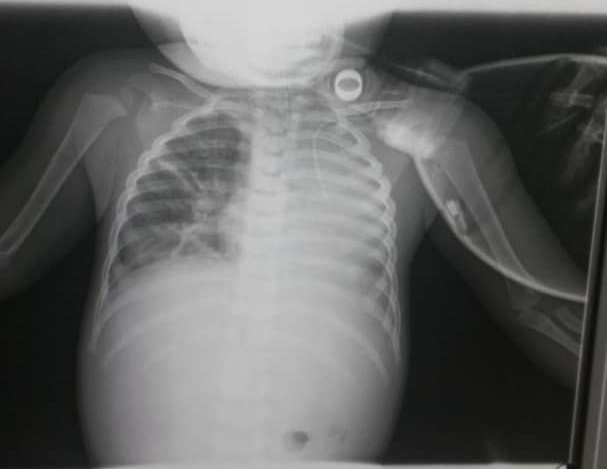

En mi lugar de trabajo, en una de esas tantas guardias, (médico pediatra), siendo las 7:00 pm acudieron a la emergencia varios adultos (familiares) con un niño 23 meses de edad masculino, cianótico y en apnea, cuya madre refirió que estaba comiendo fororo en polvo, al realizar las maniobras de resucitación pertinentes y proceder a dar apoyo ventilatorio, se constata a través de la aspiración vía tubo orotraqueal la presencia de "tacos", así como se lee, "tacos" de fororo totalmente compactado dificultando la correcta ventilación; durante varias horas se estuvo aspirando frecuentemente ya que la resistencia de la vía aérea acrecentaba por la presencia del cuerpo extraño siendo muy infructuosa el acoplamiento a la máquina de ventilación. A pesar de recibir la terapéutica adecuada (apoyo ventilatorio, manejo de terapia intensiva, broncoscopia con lavado broncoalveolar), el paciente presentó complicaciones importantes (atelectasia masiva, neumonitis, hipoxia cerebral), luego de algunos días lamentablemente fallece.

En esta imagen se visualiza una radiopacidad en campo pulmonar izquierdo, con un patrón lineal intersticial grosero derecho, lo anterior correspondiente con una atelectasia masiva izquierda y toque del intersticio pulmonar derecho (tejido de sostén del pulmón).